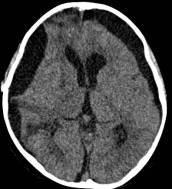

鉴于肿瘤体积超大,而且患儿间断出现意识障碍,直接作手术完全切除肿瘤的难度很大,为降低手术风险,所以我们采用先穿刺肿瘤囊减少肿瘤体积,降低颅压,二期手术争取完全切除肿瘤的策略。行肿瘤囊肿穿刺后,引流出约100多毫升囊液,肿瘤体积显著变小,见图3、图4。

图4.肿瘤囊穿刺手术后肿瘤体积减小

白色箭头示引流管